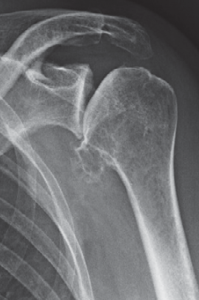

Defektarthropathie

Bei etwa 4% der Patienten mit unbehandelter Rotatorenmanschettenmassenruptur (mindestens 2 gerissene Sehnen der Rotatorenmanschette) entwickelt sich eine Arthrose des Schultergelenkes. Bei der Rotatorenmanschettenmassenruptur verlagert sich der Oberarmkopf nach vorne oben und verliert somit seine „Zentrierung“ in der Gelenkpfanne. Zusätzlich kommt es hierbei zu einer Verkürzung und Schwächung des M. deltoideus, der im Fall der Rotatorenmanschettenmassenruptur noch eine Seithebung des Armes ermöglicht.

In diesem Fall kann das Gelenk durch ein sog. inverses Prothesen-System nach Prof. Paul Grammont ersetzt werden. Hierbei wird eine „Halbkugel“ (Glenosphäre) auf die ursprüngliche Pfanne aufgeschraubt und eine konvex geformte „Humeruspfanne“ im Oberarmknochen fixiert (Abb. 48). Der Oberarm wird dadurch wieder nach „unten“ verlagert und die Funktion des M. deltoideus wird verbessert (Abb. 49).